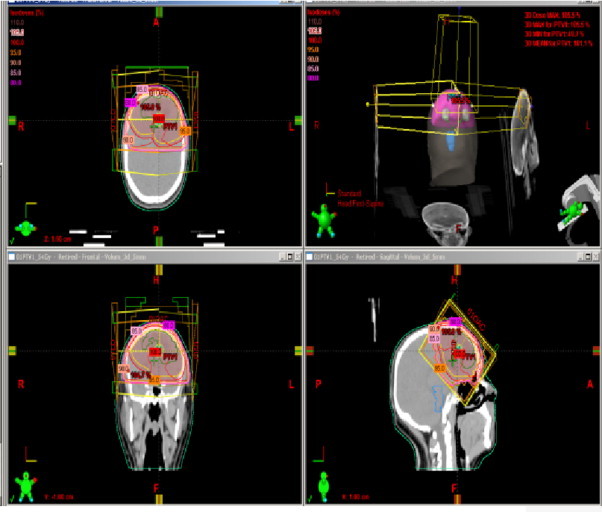

Following surgery using a Varian Clinac® 600, 6-mV photon, the patient underwent three-dimensional limited-field planning fractionated radiotherapy with a total dose of 54 Gy at 1.8 Gy/daily fraction. GTV was outlined according to MRI images fusion, and a 2-cm margin was added to define the clinical target volume (CTV), the PTV was defined as more than 0.5-cm from the CTV. Critical organs and structures were contoured.

Dosimetric characteristics are shown in Table 2 and Fig. 5.

Fig. 5.

Treatment plan and dosimetrics characteristics.